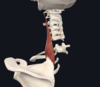

- Pectoralis minor

- 3rd-5th ribs; coracoid process of scapula

- medial and lateral pectoral nerves (C5-T1)

- stabilises the scapula (involved a bit in shoulder abduction and depression)